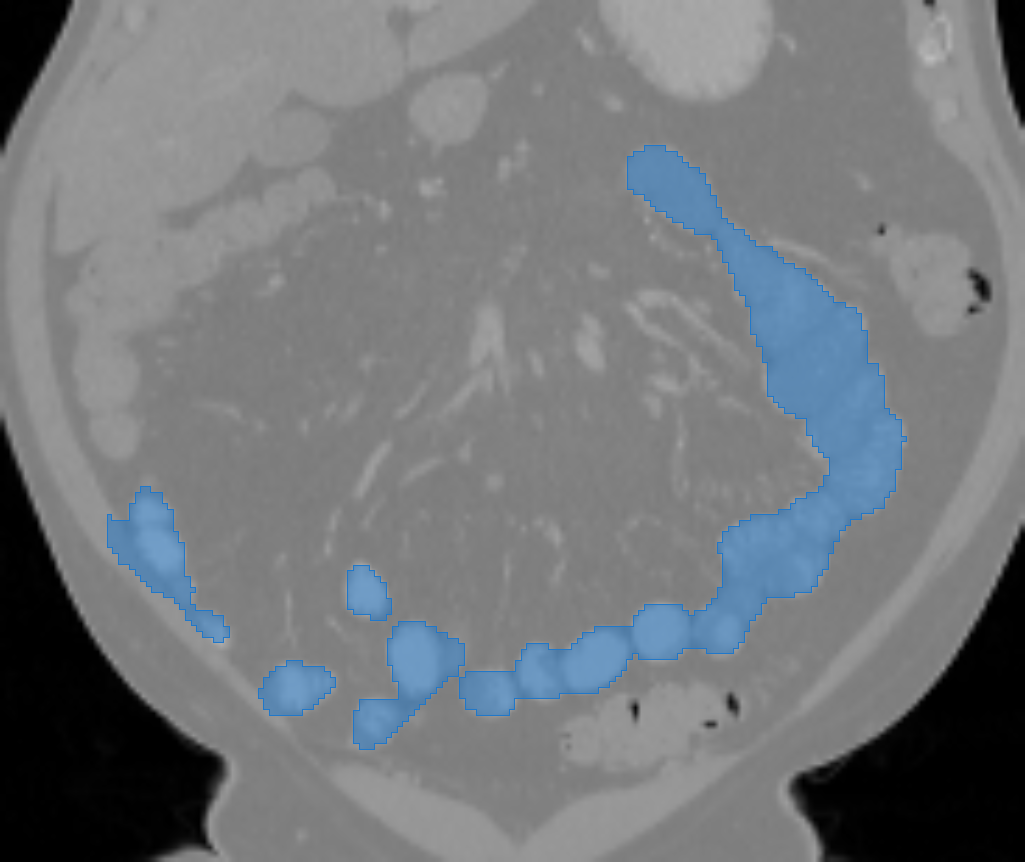

The small bowel has a cylindrical shape but also has many touchings with different parts along its path, which makes it have variable topologies across patients and time. It is inappropriate to apply a constant topological constraint to such organs. Fig. 1 shows an example of the small bowel path covered by the lumpy ground-truth (GT) segmentation.

GT labels were achieved by an experienced radiologist using 3DSlicer111https://www.slicer.org [6] based on the following steps. Firstly, the path of the small bowel is drawn as interpolated curves which connect a series of manually placed points inside the small bowel. Secondly, we grow the curves using a margin of and threshold it again using a Hounsfield unit (HU) range of . Manually drawn air pockets, which have much lower HU values, are also added during the second step. Produced errors are manually fixed in the final step. We note that this annotation procedure took one or two full days for each volume. Finally, the dataset includes the two types of labels, which are the path and segmentation of the small bowel as shown in Fig. 1.

Fig. 3 shows example segmentation results. The proposed method eliminates false positives on the large bowel by the help of the applied topological constraint. Fig. 4 further clarifies the effectiveness of the proposed method by presenting 3D rendered segmentations. The proposed method produces a more topologically correct segmentation of the small bowel with fewer false positives. Fig. 5 presents example barcode diagrams, which again show the reduced numbers of connected components and holes within the segmentation result of the proposed method.